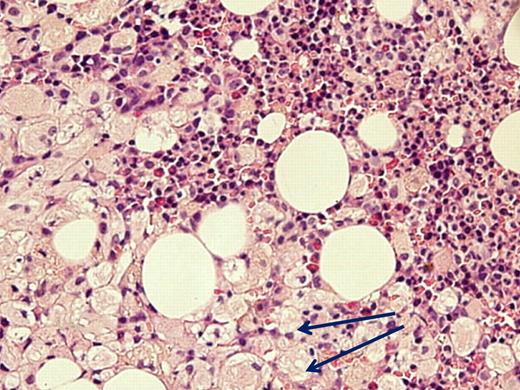

Despite advocating elimination of BM aspiration for the sole purpose of GD diagnosis, there are valid indications for this examination in GD, all related to associated diseases. (1) When the clinical presentation is atypical and differential diagnosis includes entities that can be identified/excluded by BM smear such as idiopathic thrombocytopenic purpura or acute leukemia. There are invariably patients who have 2 independently sorting disorders at presentation, such as GD and a hematologic malignancy (eg, one of our patients had a monoclonal IgA peak on routine work-up for GD; another with severe pancytopenia had acute myelogenous leukemia; Figure 1) and for whom BM examination will pinpoint the diagnosis/diagnoses. (2) When there is an unexplained deterioration in blood counts despite ERT in a symptomatic patient, or acute deterioration in a heretofore stable untreated patient, BM examination may show/exclude hematologic pathology. (3) When there is no response to ERT.

Acute myelogenous leukemia in a patient with otherwise asymptomatic GD. The Gaucher cells are indicated by arrows. Courtesy of Drs Ginette Shibi, Iris Barshack, and Hannah Maayan, Sheba Medical Center, Tel-Hashomer, Israel.

Note that for most the above-mentioned situations, particularly for unexplained cytopenias or when dealing with associated diseases wherein the large number of Gaucher cells may interfere with identifying the pathology, a biopsy should be performed in addition to aspiration to get a clearer histologic picture. In fact, not uncommonly, there will be a dry tap that would inevitably lead to a biopsy of the BM in any case.